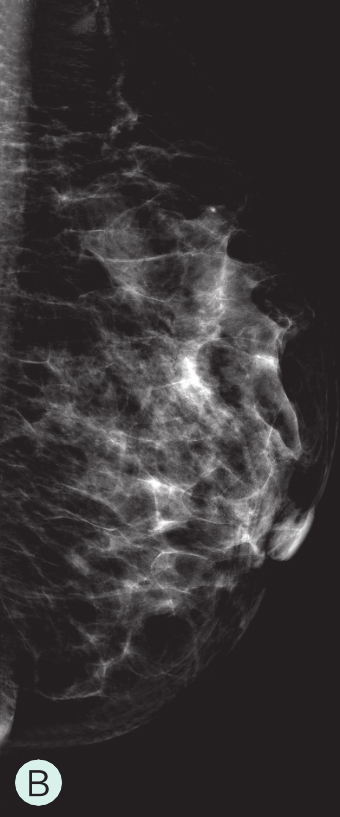

图1-3-1 乳腺X线不同乳腺密度

A.脂肪型;B.散在致密型;C.不均匀致密型;D.极度致密型